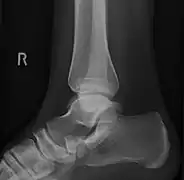

Radiological images

From left to right: Type 1, 2 and 3

Lateral projection of type 2